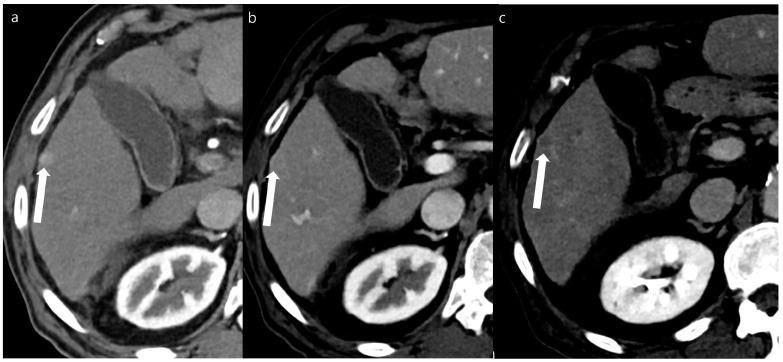

This study investigated the image quality and detectability of double low-dose hepatic multiphase CT (DLDCT, which targeted about 30% reductions of both the radiation and iodine concentration) using a vendor-agnostic deep-learning-based contrast-boosting model (DL-CB) compared to those of standard-dose CT (SDCT) using hybrid iterative reconstruction.

Compared with SDCT, a significantly lower effective dose (16.4 ± 7.2 mSv vs. 10.4 ± 6.0 mSv, 36.6% reduction) and iodine amount (350 mg iodine/mL vs. 270 mg iodine/mL, 22.9% reduction) were utilized in DLDCT. The mean overall arterial and portal phase image quality scores of DLDCT were significantly higher than SDCT (arterial phase, 4.77 ± 0.45 vs. 4.93 ± 0.24, AUC 0.572 [95% CI, 0.507-0.638]; portal phase, 4.83 ± 0.38 vs. 4.92 ± 0.26, AUC 0.535 [95% CI, 0.469-0.601]). Furthermore, DLDCT showed significantly superior quantitative results for the lesion contrast-to-noise ratio (7.55 ± 4.55 vs. 3.70 ± 2.64, < 0.001) and lesion detectability (0.97 vs. 0.86, = 0.003).

In patients with chronic liver disease, DLDCT using DL-CB can provide acceptable image quality without impairing the detection and evaluation of hepatic focal lesions compared to SDCT.